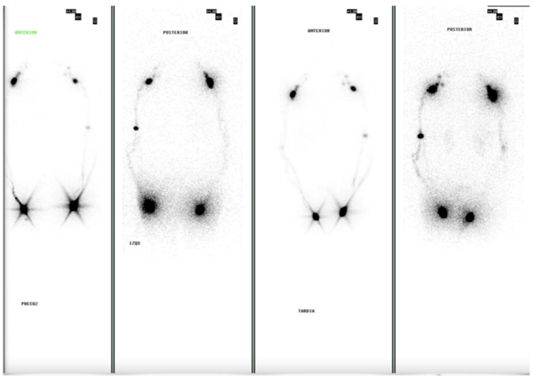

The PET-CT scan showed supra- and infradiaphragmatic lymphadenopathy, hypermetabolic thyroid lesions, and a left axillary lymph node with significant uptake (Figure 3). Colonoscopy revealed only diverticulosis. Lymphoscintigraphy of the upper and lower limbs was normal (Figure 4). Cytometry of the pleural fluid showed a predominance of T lymphocytes, and the peripheral blood smear showed no abnormalities.

Figure 4: Lymphoscintigraphy. Physiological distribution with early tracer migration and evidence of deep lymphatic vessels with absence of subcutaneous migration.